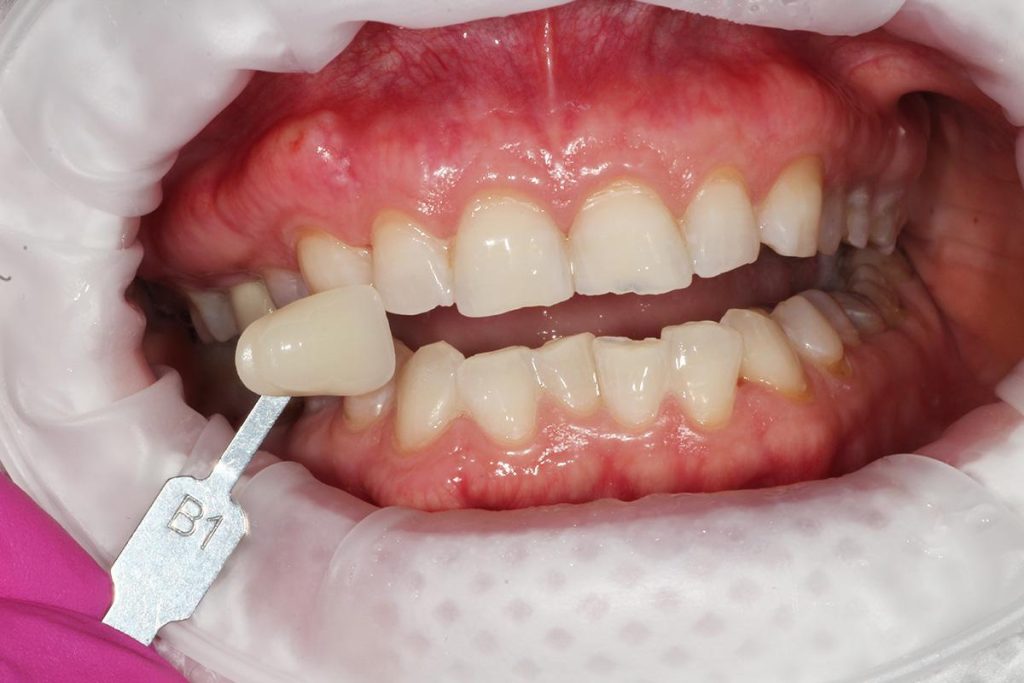

- Przeprowadziliśmy wybielanie zębów, aby uzyskać idealny odcień.

- Wykonaliśmy pełnoceramiczne licówki na górne jedynki.

- Zmieniliśmy wygląd kła przy pomocy licówki, aby wyglądał jak naturalna dwójka.

Całe leczenie trwało tylko 3 miesiące, a efekt końcowy przeszedł najśmielsze oczekiwania.

Licówki i korona na implancie wykonane przez laboratorium Dentalscan.